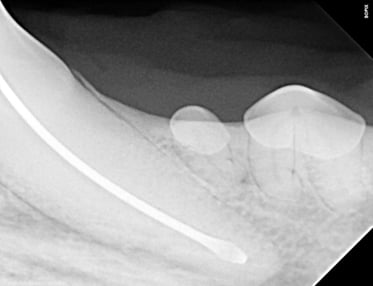

Below: Radiograph of crown with final oil and restorative material

%20Case%202%20-%20July%202024/Final%20fill%20and%20Restoration%20of%20Crown%20RCT.jpg?width=373&height=287&name=Final%20fill%20and%20Restoration%20of%20Crown%20RCT.jpg)

Next, a glass ionomer intermediary layer was applied, followed by light-curing and acid-etching to ensure optimal adhesion. An eighth-generation bonding agent (unfilled resin) was then meticulously applied and cured, with additional filled composite layers utilized to effectively seal the access site.

For the final restoration, Omnichroma flowable restoration material was applied and light-cured, ensuring a seamless integration with the surrounding tooth structure. The restoration was then meticulously smoothed to achieve an impeccable finish.